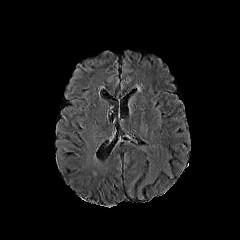

Refer to caption

(a) Truth

(b) Synthesized lesion

(c) Truth

(d) Synthesized lesion

Figure 13: Synthesis of a lesion 𝒢N2A(x)subscript𝒢N2A𝑥\mathcal{G}_{\rm{N2A}}(x) in two healthy MRI x𝑥x.

We leverage the trained 𝒢N2Asubscript𝒢N2A\mathcal{G}_{\rm{N2A}} to synthesize abnormal-looking images on BratS18 datasets. Two examples are shown in Figure 13. We observe that the tumor is synthesized near the brain boundary in the second example. In training 𝒢N2Asubscript𝒢N2A\mathcal{G}_{\rm{N2A}}, the discriminator 𝒟Asuperscript𝒟A\mathcal{D}^{\rm{A}} encodes the core patterns of the real abnormal-looking images data, which can avoid having lesions being generated in physiologically unreasonable locations. We observe the generator 𝒢N2Asubscript𝒢N2A\mathcal{G}_{\rm{N2A}} produces realistic lesion-containing MR images.